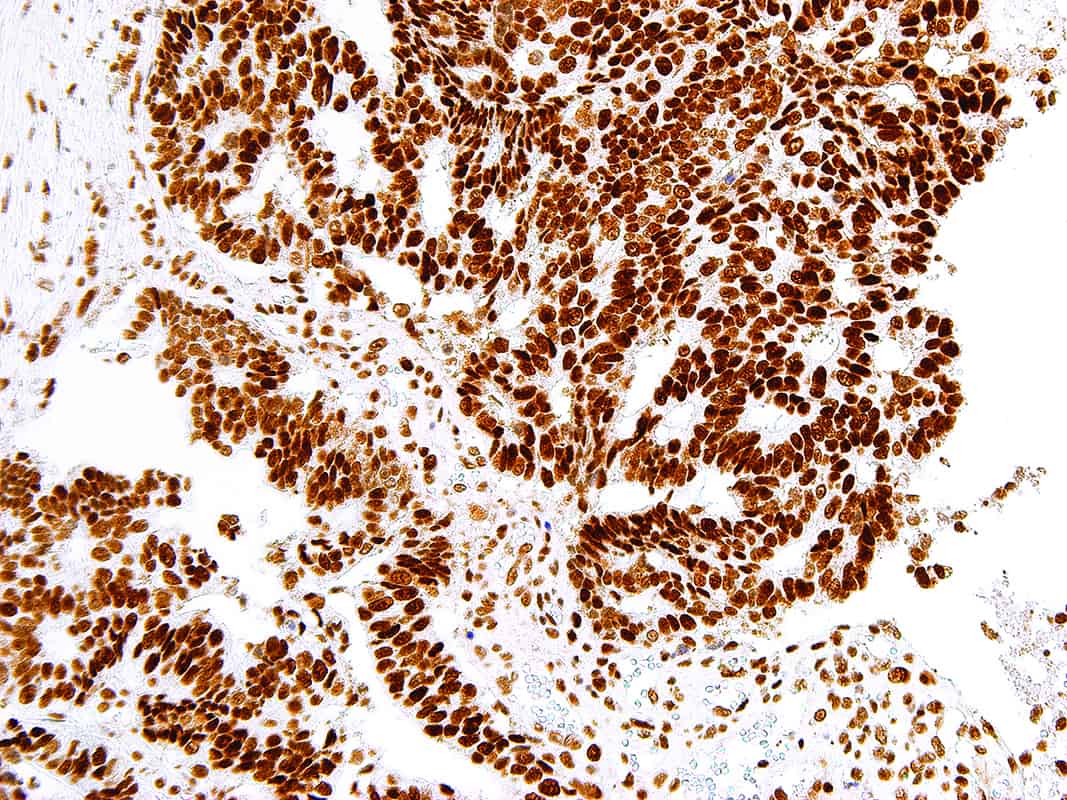

MutS Homolog 2 (MSH2) is a protein involved in the mismatch-repair pathway. This protein is commonly associated with hereditary non-polyposis colorectal cancer, and mutations in this gene are correlated with the development of sporadic colorectal carcinoma. Expression levels of MSH2 are abnormally low in a high percentage of patients with microsatellite instability, as well as endometrial and ovarian cancers. Use of Anti-MSH2 is optimized when paired in an IHC panel with antibodies against MSH6, MLH1, and PMS2. Reports have shown Anti-MSH2 to be useful in the detection of the protein in a number of normal and neoplastic tissues, and for identifying a loss of MSH2 in tumors that are microsatellite-unstable.

| Positive Control | Colon Mucosa, Colon Carcinoma |